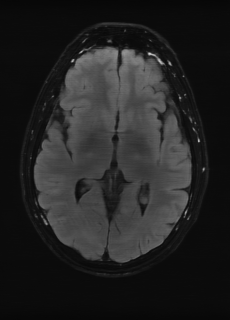

As we observe from the right image in Fig. 2, our BRM, both from MIMO and SISO settings, predicts the performance of dedicated models with a high correlation. We further choose the best three , and perform the last stage of fine-tuning accordingly to (6). A visual evaluation on real data is shown in Fig. 3. For simulated data, please refer to the Supplemental Material section.

Base on the best performing , we perceive that among , , and FLAIR, the results are best when is sampled the most. We suggest that this makes intuitive sense as images provide the best contrast out of the three sequences, which can compensate for the details lost in other images. The same observation can be made on the simulated data, where both and FLAIR show good contrast. When the time setting is changed to non-uniformity, we can see that our search for the best sampling strategy reflects the change. is sampled more as a result of faster acquisition time, while is still sufficiently sampled.

| Sequence | LR | SISO | MIMO | MIMO tuned | GT |

|---|---|---|---|---|---|

(a) 34.38/0.9371

(a) 34.38/0.9371

|

(b) 42.42/0.9883

(b) 42.42/0.9883

|

(c) 44.60/0.9920

(c) 44.60/0.9920

|

(d) 45.50/0.9940

(d) 45.50/0.9940

|

(e) PSNR/SSIM

(e) PSNR/SSIM

|

|

(f) 29.74/0.8903

(f) 29.74/0.8903

|

(g) 36.25/0.9734

(g) 36.25/0.9734

|

(h) 36.42/0.9752

(h) 36.42/0.9752

|

(i) 37.70/0.9832

(i) 37.70/0.9832

|

(j) PSNR/SSIM

(j) PSNR/SSIM

|

|

(k) 39.89/0.9311

(k) 39.89/0.9311

|

(l) 43.94/0.9864

(l) 43.94/0.9864

|

(m) 44.74/0.9883

(m) 44.74/0.9883

|

(n) 45.49/0.9894

(n) 45.49/0.9894

|

(o) PSNR/SSIM

(o) PSNR/SSIM

|